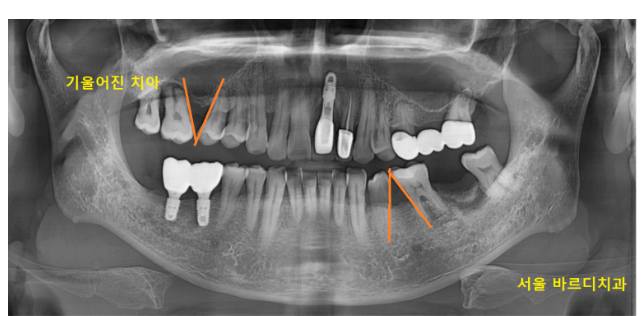

예전에 치아를 뽑고 방치하면

이동이 발생하기 때문에 바로 치료를 해야한다는 글을 작성해드린 적이 있는데요.

오늘 환자분도 이가 빠진채로 오랫동안 사용하신 듯 합니다.

치아들이 옆으로 픽픽

쓰러져 있는 상황이었거든요~

어금니가 원래 있던 자리를 벗어나다 보니

발생한 문제점

하나씩 살펴보겠습니다~!

231216

먼저 윗니 어금니

이제는 임플란트로 치료를 하고 싶어도

못하는 상황이 되었습니다.

11,12,13,14,15 적혀있는 것은 치아 번호입니다.

순서대로 있어야 하는데..

15 다음이 17이 있죠?

16 어금니가 안보입니다.

이 어금니가 오래전 발치된 것인데

시간이 오래 지나다 보니

치아 빠진 공간이 좁아졌습니다.

양 옆 치아(15번 17번)가 쓰러지기도 많이 쓰러졌고요.

임플란트를 심을 수 있는 공간이 나와야

나사가 들어가는데

전혀 공간이 보이지 않습니다.